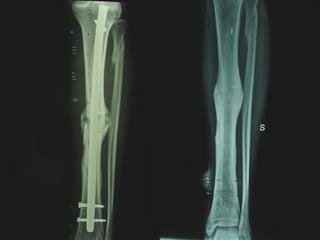

Dal Gennaio 2000 al Febbraio 2006 abbiamo trattato 167 fratture chiuse  con placca percutanea  in 164 pazienti :  27 lesioni diafisarie di gamba, 12 piloni tibiali ,  11 fratture prossimali di tibia, 36 fratture sovracondiloidee di femore, 17 fratture diafisarie di femore, 43 fratture metaepifisarie prossimali di omero, 21 diafisarie d’omero.  156 guarigioni 8 fallimenti

Dal Giugno 2002 al Dicembre 2004 abbiamo trattato 5 fratture esposte: 3 di tibia e 2 di ulna 5 guarigioni

I buoni risultati ottenuti dipendono da 5 punti fondamentali:   una accurata riduzione percutanea della frattura  precise vie di accesso  l’utilizzo della placca che consenta il più lungo braccio di leva possibile il pretensionamento della placca  una sintesi con un ridotto numero di viti